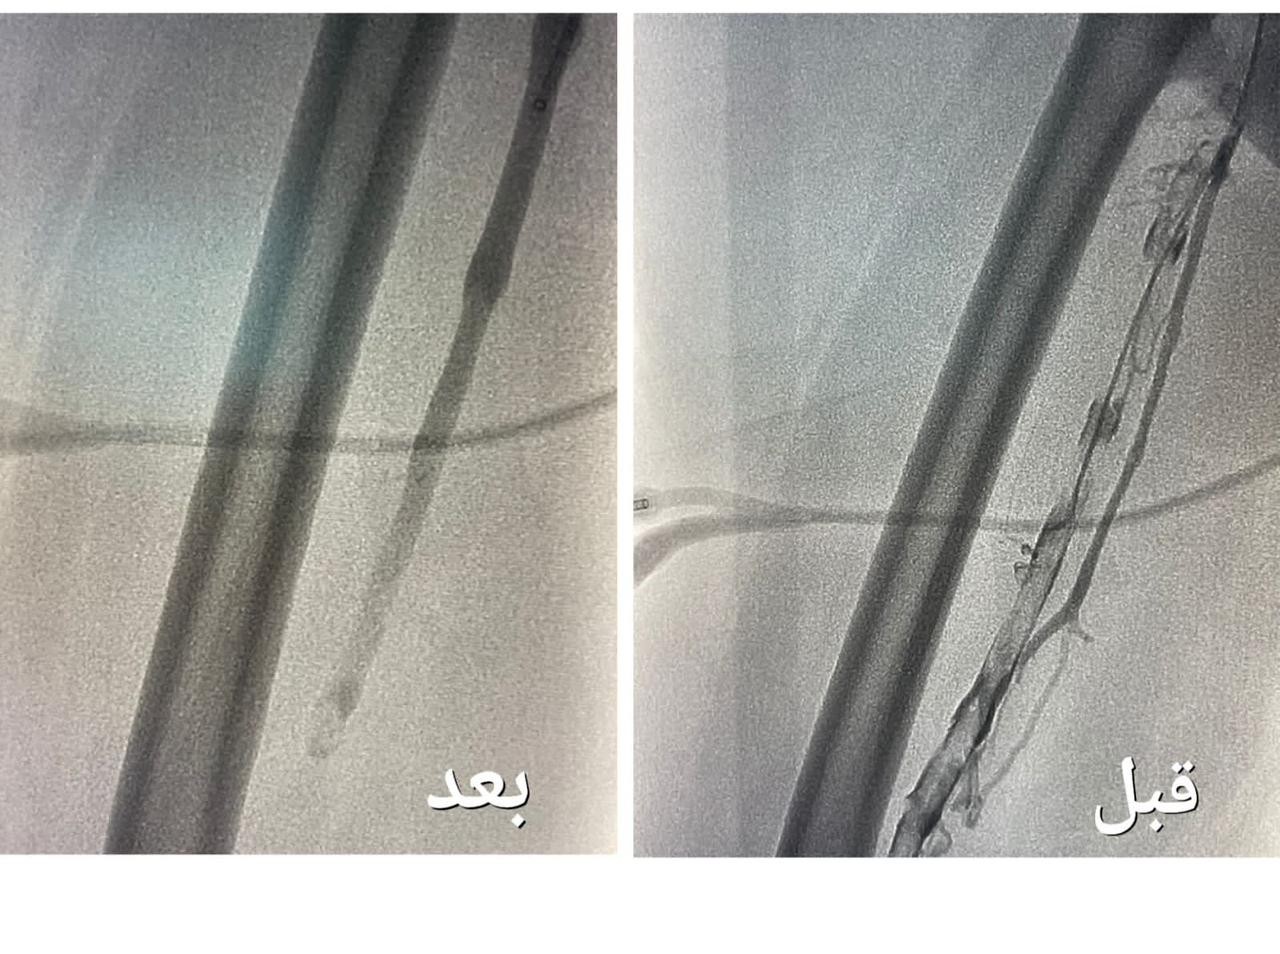

وأضافت أن الفرق الطبية أسهمت أيضاً في إنقاذ حياة حاج بنجلاديشي تعرض لجلطة قلبية حادة وأظهرت الفحوصات الطبية التي أُجريت له إصابته بجلطة حادة في عضلة القلب مع وجود انسداد كامل في الشريان الأيمن التاجي، و لخطورة الحالة تم إجراء عملية قسطرة علاجية عاجلة تم فيها فتح الشريان الأيمن وتوسيعه، ليتم متابعة الحالة مع الفرق الطبية والتمريضية لحين استقرار الحالة وخروجها ومغادرة أرض الوطن بالسلامة.